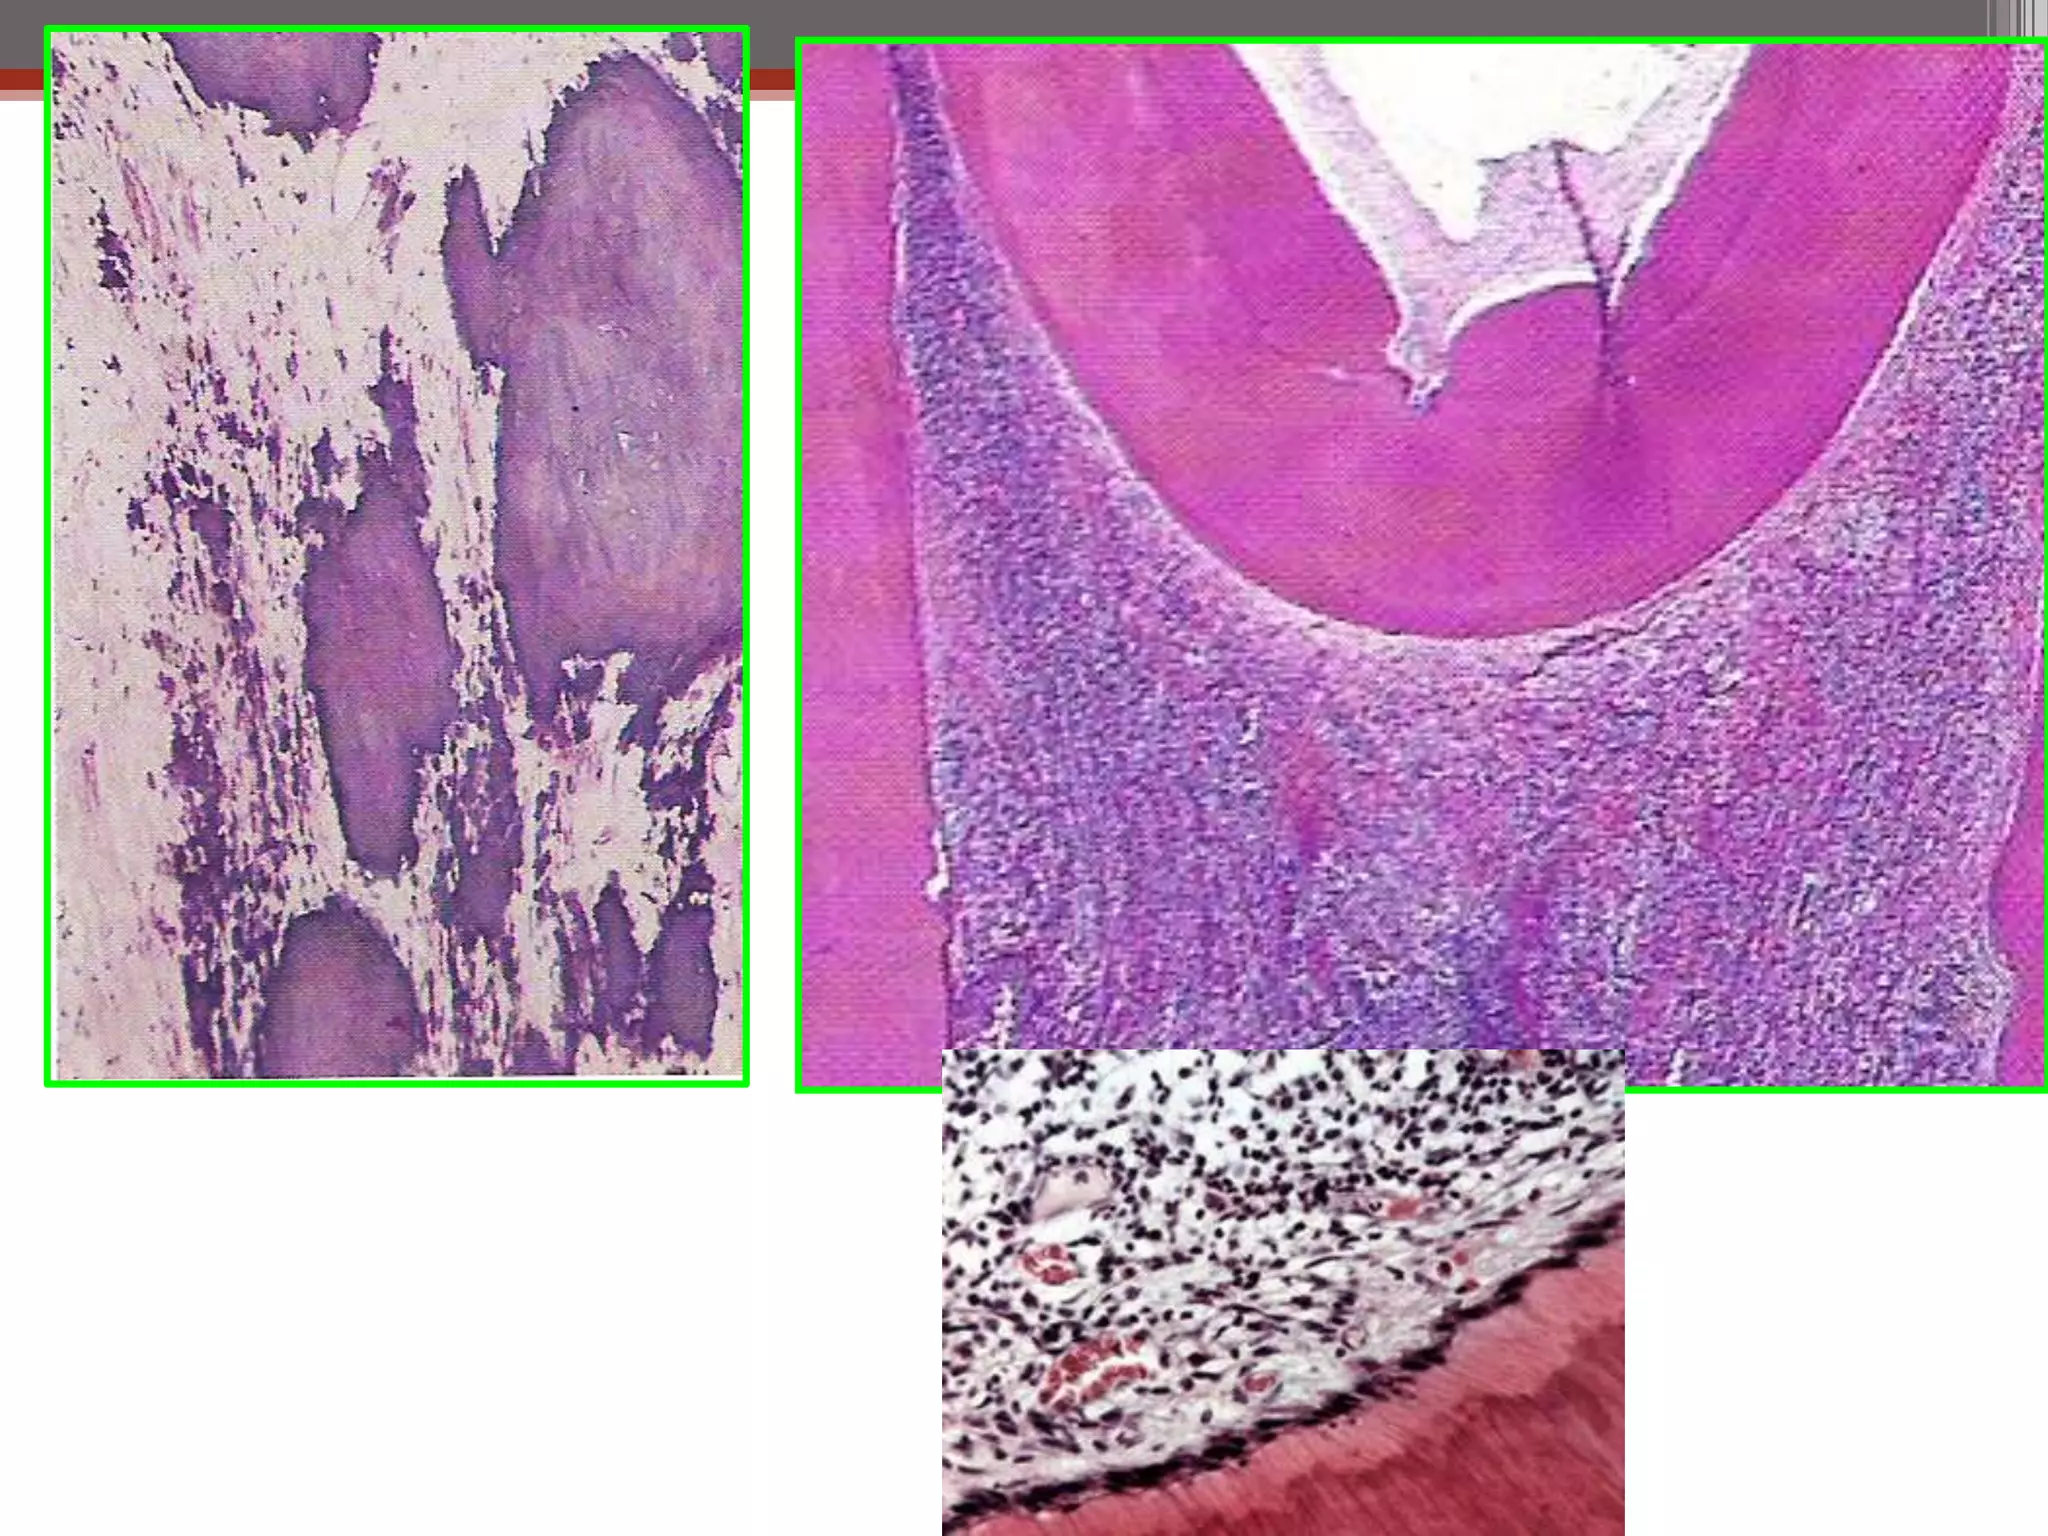

Periapical inflammation

Periapical

Granuloma

abscess

Chronic abscess or

osteomyelitis

Cellulitis

Skin or mucosal sinus

Bacteremia

Cyst

Periapical inflammation Periapical Granuloma Periapical abscess Chronic abscessor osteomyelitis Cellulitis Skin or mucosal sinus Bacteremia Periapical Cyst